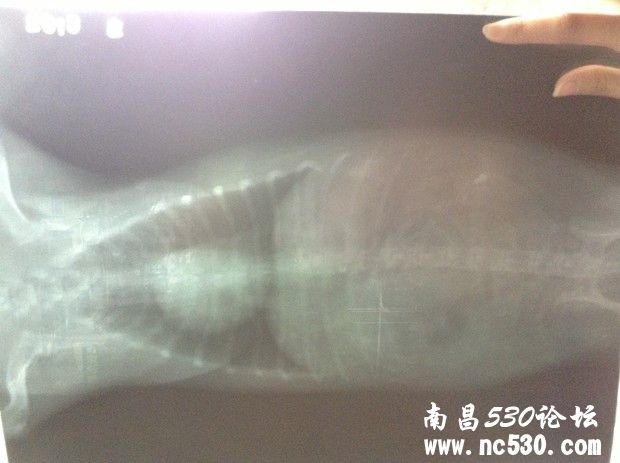

狗狗咳嗽已好几个月,之前一直是偶尔一两声卡卡干咳声,到最近转变成一连串咳嗽,明显加重,而且咳嗽声音变化了。前天带去医院看,打了X光,查了血常规和电解质(这个查没查我不知道医生也没说但收了费)。然后医生说心脏有点点肥大,应该是心脏顶到气管造成的咳嗽。别的血常规这些都正常,血压也正常。就说以后给它吃皇家心脏处方狗粮,然后开了几颗扩张支气管的药(肺心康),两三天的量。就这样了。但是狗狗回来还是一直咳,特别是晚上,咳得很可怜,咳到最后还象卡痰那样的象有痰吐不出来似的。我就是想知道,我家狗狗到底是不是因为心脏原因引起的咳嗽,还是会是别的?难道就让它这么咳下去么?皇家心脏处方狗粮现在买不到,还是吃的平常的,因为说它有点点偏胖就给它吃得很少减了量。它现在饿跑来想吃我都不敢给它吃,请问这样让它少吃的做法对么?还是吃一般的狗粮可以么?

还有就是今天回来仔细看片子,发现下图那块(喉咙还是气管那下面我圈起来的地方)有块东西,也不知道是片子是脏的还是它身上的?特意放上来请各位专家医生看看。说实话,那天医生也没和我讲清楚,连查血那些的单子也没给我,病历也未给写,片子我还是走的时候要求要的。